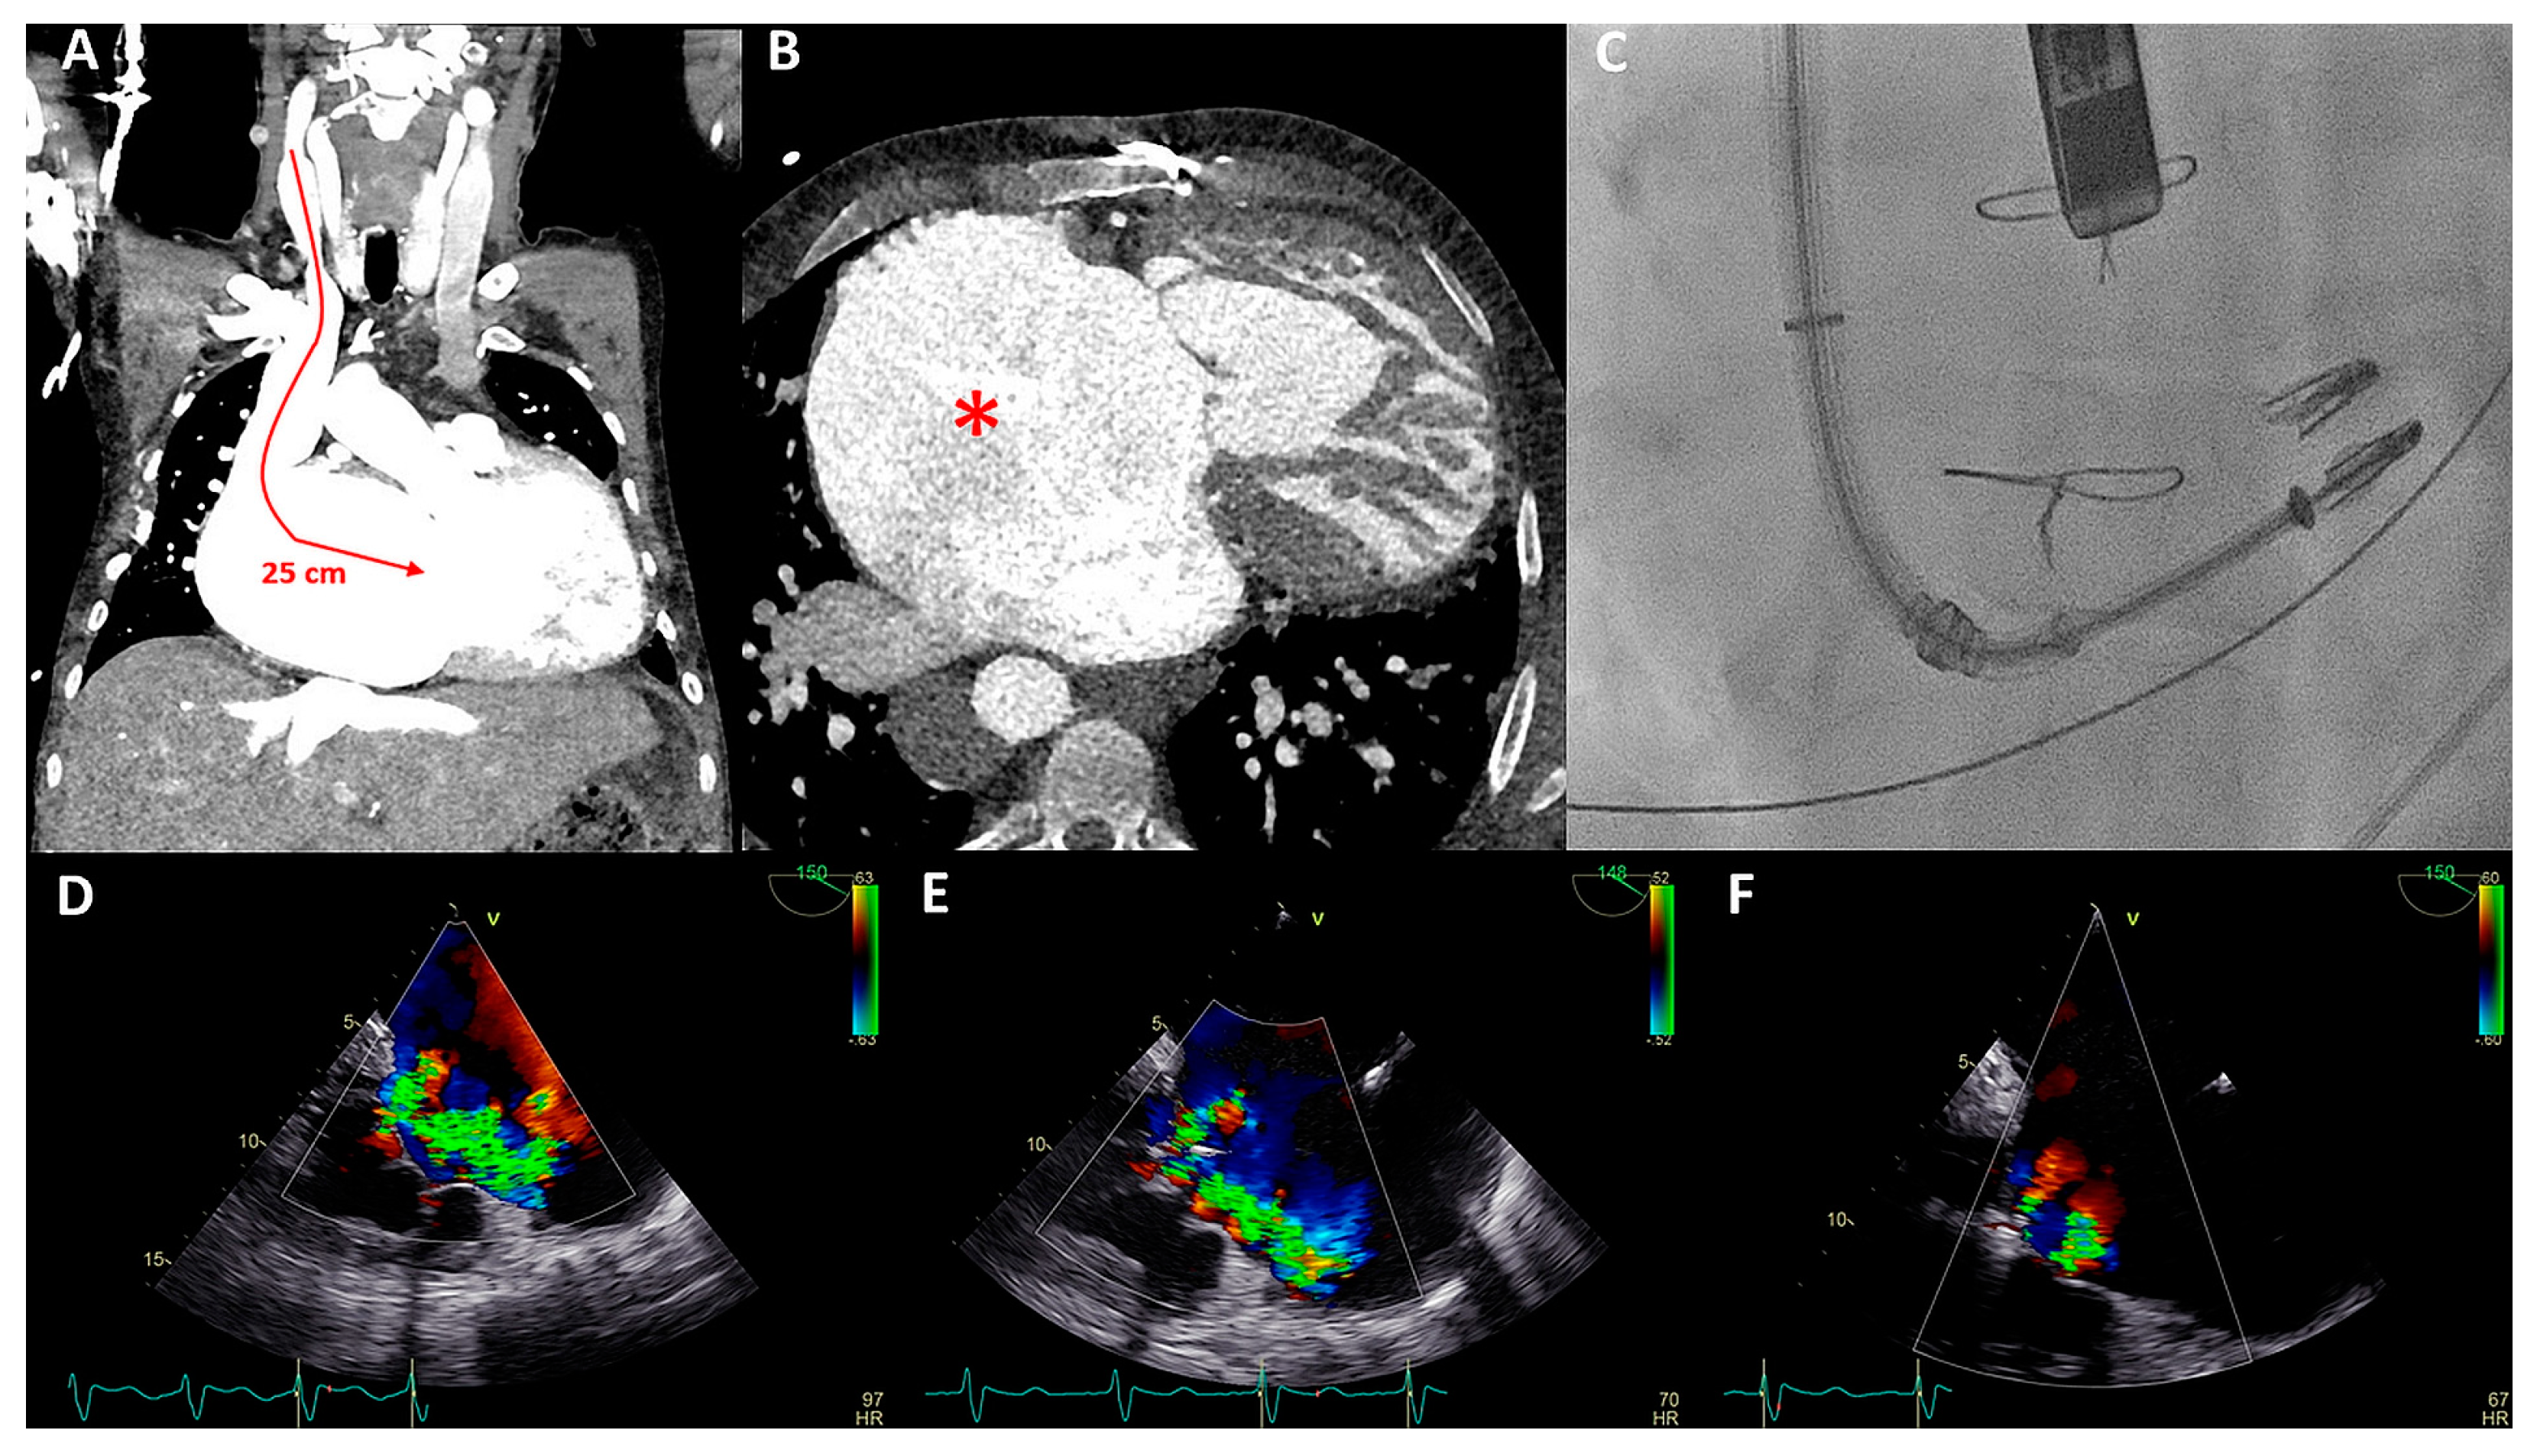

Figure 7.

(A) Color Doppler modified parasternal right ventricular (RV) inflow view shows severe tricuspid regurgitation (TR) with a wide vena contracta (arrow) and leakage jet reaching the inferior vena cave (IVC). (B) Apical four-chamber view shows tricuspid valve (TV) annulus dilatation (dash line, 46 mm) and impingement by the RV pacemaker lead (arrow). (C) Left inferior oblique fluoroscopic view of the Cardioband (arrow) annulus reduction procedure (asterisk). (D) Anteroposterior fluoroscopic view shows the two XTW clips (arrows) implanted. (E,F) Modified apical four chamber color Doppler views showing mild (-moderate) residual TR and inflow through the TV (mean gradient of 3 mmHg).

Both procedures were performed in sequential order under general anesthesia, by means of right femoral access and fluoroscopy and transesophageal echocardiographic guidance (Figure 7C,D). A total of 15 anchors were used for the Cardioband annular reduction (Edwards Lifesciences, USA) reducing the annulus dimensions to 28 × 27 mm. Yet, moderate-severe TR persisted and the second procedure was planned for the patient. She underwent the placement of two TriClips (Abbott, IL, USA), resulting in reduction of TR to mild-moderate and a slightly elevated inflow gradient of 3 mmHg over de TV (Figure 7E,F). No periprocedural complications were documented. At 16 months follow-up, the patient remains in NYHA functional class II and is euvolemic. No heart-failure-related admissions occurred since the TV interventions.